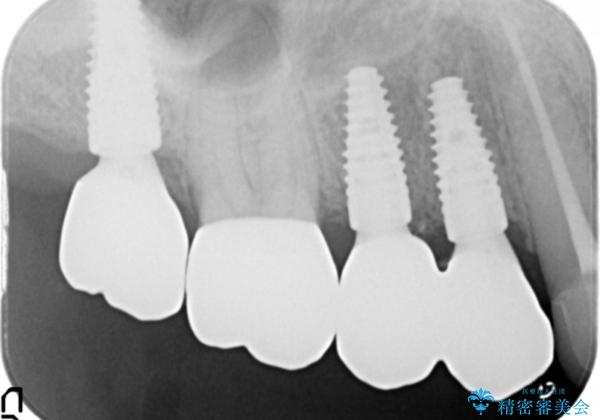

保存の難しい歯の抜去を行ったのち、咬合力にしっかりと耐えうる補綴設計としてブリッジや入れ歯ではなくインプラント治療を計画します。

- 110万円 (インプラント×3 アバットメント×3 クラウン×4)費用は治療当時の料金となります

噛む力の強い方は、ブリッジやクラウンが破損するだけでなく支える歯が割れてしまったりすることがよくあります。

今回はインプラントによる機能回復を行いましたが、過大な力から歯やインプラントを守るためにナイトガードの装着が必要です。